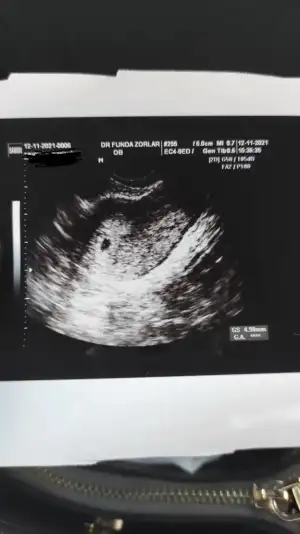

Caglunal Caglunal Sat 8 Ekim. İkinci çocuk. Yaş 37. İstanbul. Tahmini tarih 15 Temmuz :KK36:

Bugün doktora gittim. Ultrasonda keseyi gördüm. Ama henüz çok yeni 10 gün sonra tekrar kontrol var.

Doktor detay vermedi. Zaten tatile geldiğim yerde bir devlet hastanesiydi. Özel hastane gibi değil tabi. Ben "enfeksiyon belirtisi var sarı akıntım var" dedim ama umursamadı "flora değişikliğinden de olabilir" dedi. İdrar testi istemedi. Oğlumda ben istemeden yaptırmıştı ve ilaç kullanmam gerekti.